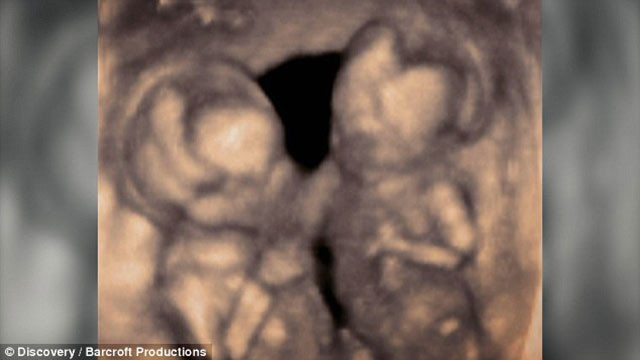

Hindistan bir bebek karnına yapışık parazit ikiziyle dünyaya geldi. Sadece 9 günlükken hayati operasyon için bıçak altına yatmak zorunda kaldı.

Daily Mail'in haberine göre Hemlata Singh, Sonni ismini verdiği sağlıklı bir bebek dünyaya getirdi ancak bebek karnında yapışık parazit ikiziyle geldi. Üstelik Sonni'nin kalbinden karaciğerini paylaştığı deforme parazit ikizine kan pompalanıyordu.

Beyni gelişmeyen bebeğin bağırsakları veya midesi de yoktu. Bu da hayatta kalma şansının olmadığı anlamına geliyordu. Ayrıca ikiz kardeşinin hayatını riski atıyordu.